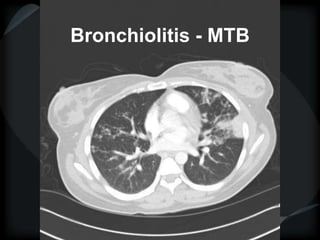

HRCT - Nodular Pattern

BRONCHIOLAR

 Centrilobular nodules: small airways of secondary lobule

 1-3mm away from pleura

 Not sub pleural

 Not on fissures or septae

Primary bronchiolar disease Mixed bronchiolar

Sharp branching nodules Peribronchiolar

Tree-in-bud ground glass nodules+/-tree-in-bud

MAI, MTB sub acute HP

Aspergillus respiratory bronchiolitis - ILD

DPB, DAB LIP

Follicular bronchiolitis Early LCH

Immune bronchiolitis – UC metastatic Calcification (CRF)

mineral dust bronchiolitis

nylon flock workers disease

Secondary to bronchiectasis

silicosis

Tree-in-Bud Appearance

Bronchiolitis

Rare- tumor cell emboli – intralobular artery

Bronchiolitis - MTB